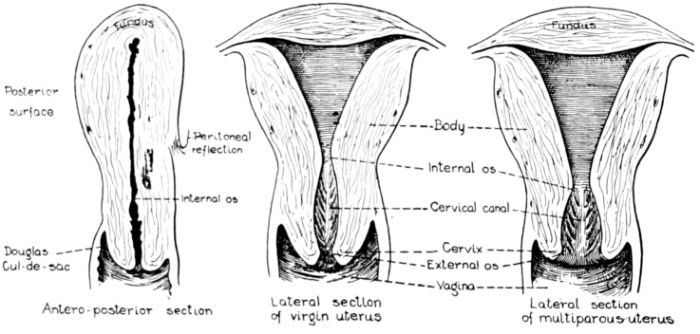

| 11. | Diagrams of sections of virgin and multiparous uteri | 32 |

Fig. 11.—Diagrams of sections of virgin and multiparous uteri.

The uterus as a whole is comprised of three parts: the fundus, that firm, rounded, head-like part above; the body, or middle portion, and the cervix, or neck, below. It is in the body and cervix that we find the long, narrow uterine cavity, divided by a constriction into two parts. The cavity of the body is little more than a vertical slit, being so flattened from before backward 33that the anterior and posterior surfaces are nearly if not quite in apposition. It is somewhat triangular in shape with an opening at each angle. (Fig. 11.) The lower of these openings leads into the cavity of the cervix through a constriction termed the internal os, while at the cornua, or two upper angles, are the openings into the Fallopian tubes.

The cavity of the cervix is spindle-shaped, being expanded between its two constricted openings, the internal os above and the external os below, which opens into the vagina. The external os in the virgin is a small round hole but has a ragged outline in women who have borne children.

This oblong, muscular body, the uterus, is suspended obliquely in the centre of the pelvic cavity by means of ligaments. In its normal position the entire organ is slightly curved forward, or ante-flexed, the fundus being directed upward and forward and the cervix pointing down and back. This position is affected by a distended bladder or rectum, and also by postural changes in the body as a whole. The cervix protrudes into the anterior wall of the vagina for about one-half inch and almost at right angles, since the vagina slopes down and forward to the outlet.